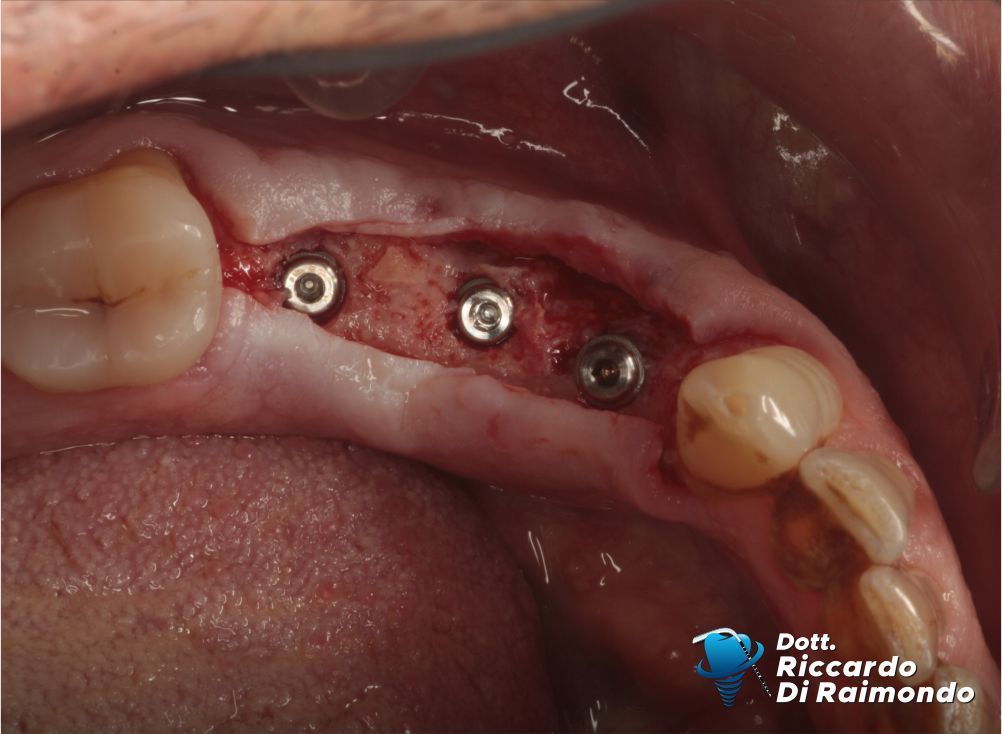

Dopo circa 5 mesi dall’estrazione e preservazione alveolare, ho proceduto alla riapertura della zona operata precedentemente, osservando una ottimale disponibilità ossea non solo in altezza ma soprattutto in spessore per poter inserire 3 impianti dentali.

Durante il Trattamento